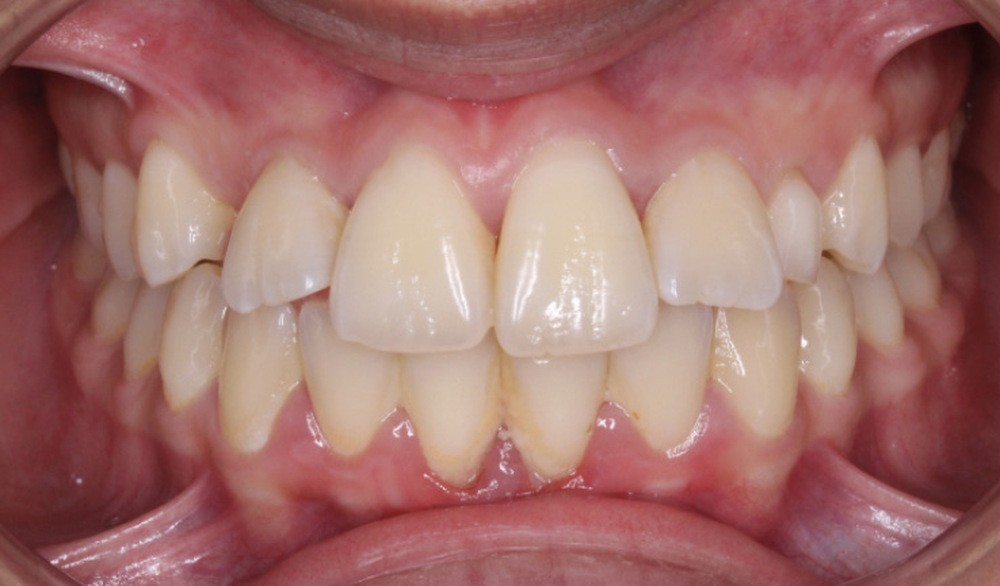

La patiente âgée de 14 ans et 6 mois le jour du bilan se présente en consultation pour une gêne esthétique au niveau de ses dents maxillaires : « trop en avant et avec des espaces ».

Les examens cliniques et radiologiques ont mis en évidence l’inclusion de 13 et 23, une légère classe II bilatérale par perte d’ancrage, un biotype parodontal de type IV de Maynard et Wilson avec une insertion du frein mandibulaire antérieur papillaire, une biproalvéolie et une typologie hypodivergente. La réalisation d’un examen tridimensionnel a permis de confirmer la localisation palatine de 23 et vestibulaire de 13 ainsi que de visualiser l’étendue des résorptions radiculaires touchant 12, 21 et 22 (fig. 1a-i).